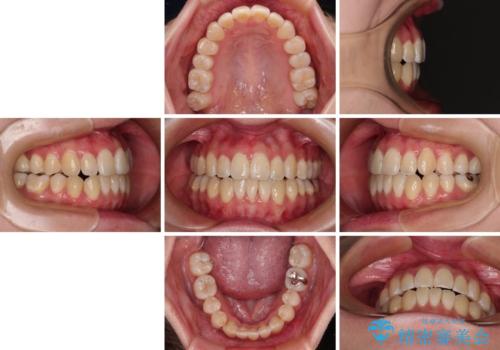

- 上下前歯の隙間と、外側を向いていて歯磨きのしにくい奥歯を気にして来院された患者様です。

下顎前歯が1本欠損しており、上下アーチはアンバランスとなりますが、インビザラインを用いて上下の隙間を改善しながら歯列を整えることとしました。

外側を向いている奥歯は、内側にアンカースクリューを埋入して牽引の固定ゲント氏、部分的にワイヤー装置を用いることで歯列に納めることとしました。

下顎前歯の1本欠損により左右の咬合が不安定となり、治療経過で噛みにくい状態が続きましたが、最終的には違和感なく噛めるようになりました。